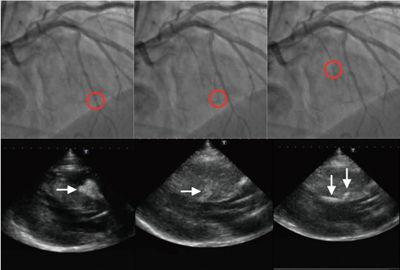

図3は、対角枝から分岐する中隔枝が冠動脈CT画像で確認された症例であり、第一中隔枝からの分枝を含めて2本の枝がCT画像上での焼灼対象と考えられた。コントラストエコーでも、同2枝に関しては左室流出路の心筋内膜側を灌流していることが確認されたが、第一中隔枝の本幹は右室側を灌流しており、焼灼対象ではなかった(図4)。術直後に施行された冠動脈CT検査では、エタノール動注された2枝の末梢側を中心に焼灼心筋部位が遅延造影されており、コントラストエコーでの灌流域と一致していた(図5)。このような症例を経験し、われわれは、より正確に焼灼対象となる中隔枝を選択するには冠動脈CT画像の活用が有効であると考えている。

図3 中隔枝に着目したCT画像(左)とカテーテル造影画像(右)

赤円部分がCT画像から焼灼対象に選択された枝で、左側の枝は対角枝から分岐していた。

図4 焼灼対象の中隔枝に対して行われたコントラストエコー像

CTで選択された2枝は、左室流出路の心筋内膜側を灌流しているが(中、右)、第一中隔枝の本幹は右室側を灌流していた(左)。